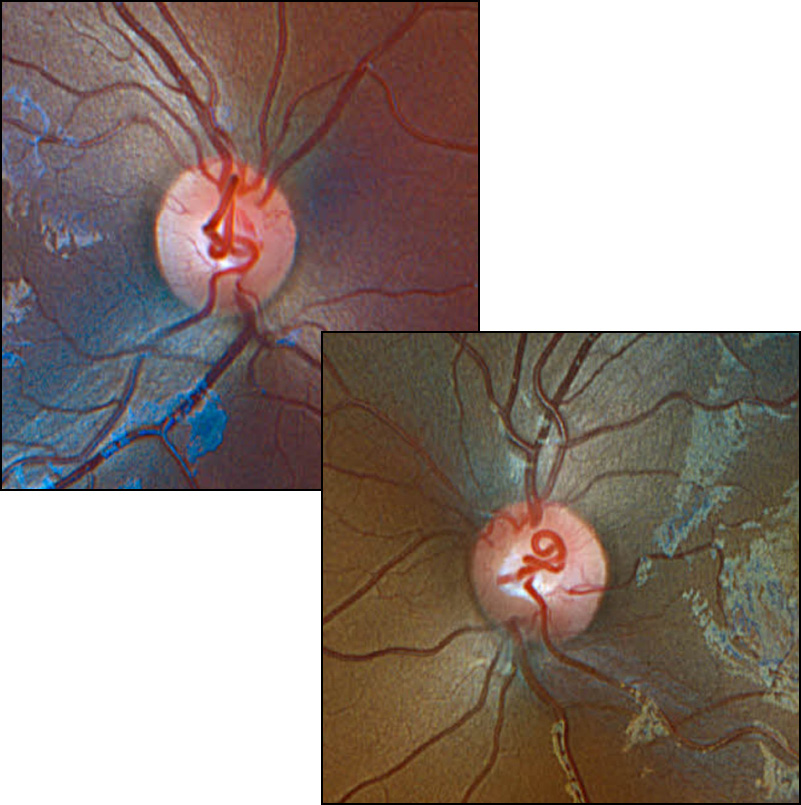

Proliferative diabetic retinopathy

Bilateral prepapillary vascular loops in a pediatric patient